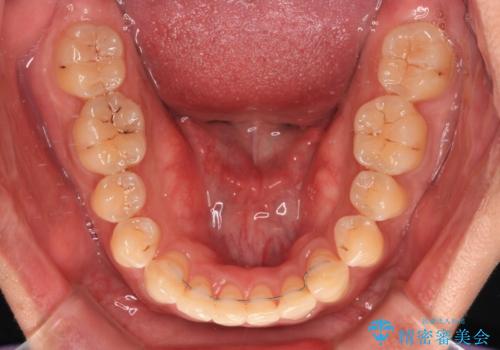

予定していた期間より長くかかりましたが、1年強できれいな歯列に仕上がりました。